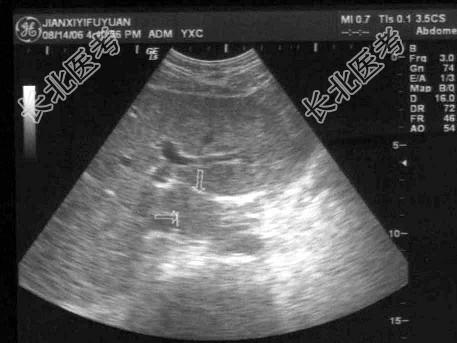

- 单项选择题肋缘下斜切面显示门静脉左支时,可显示肝尾叶位于 ( )

A、门静脉左支矢状段与胆囊之间

B、门静脉左支横段与下腔静脉之间

C、肝门静脉与肝静脉之间

D、肝右静脉与胆囊之间

E、以上都不是